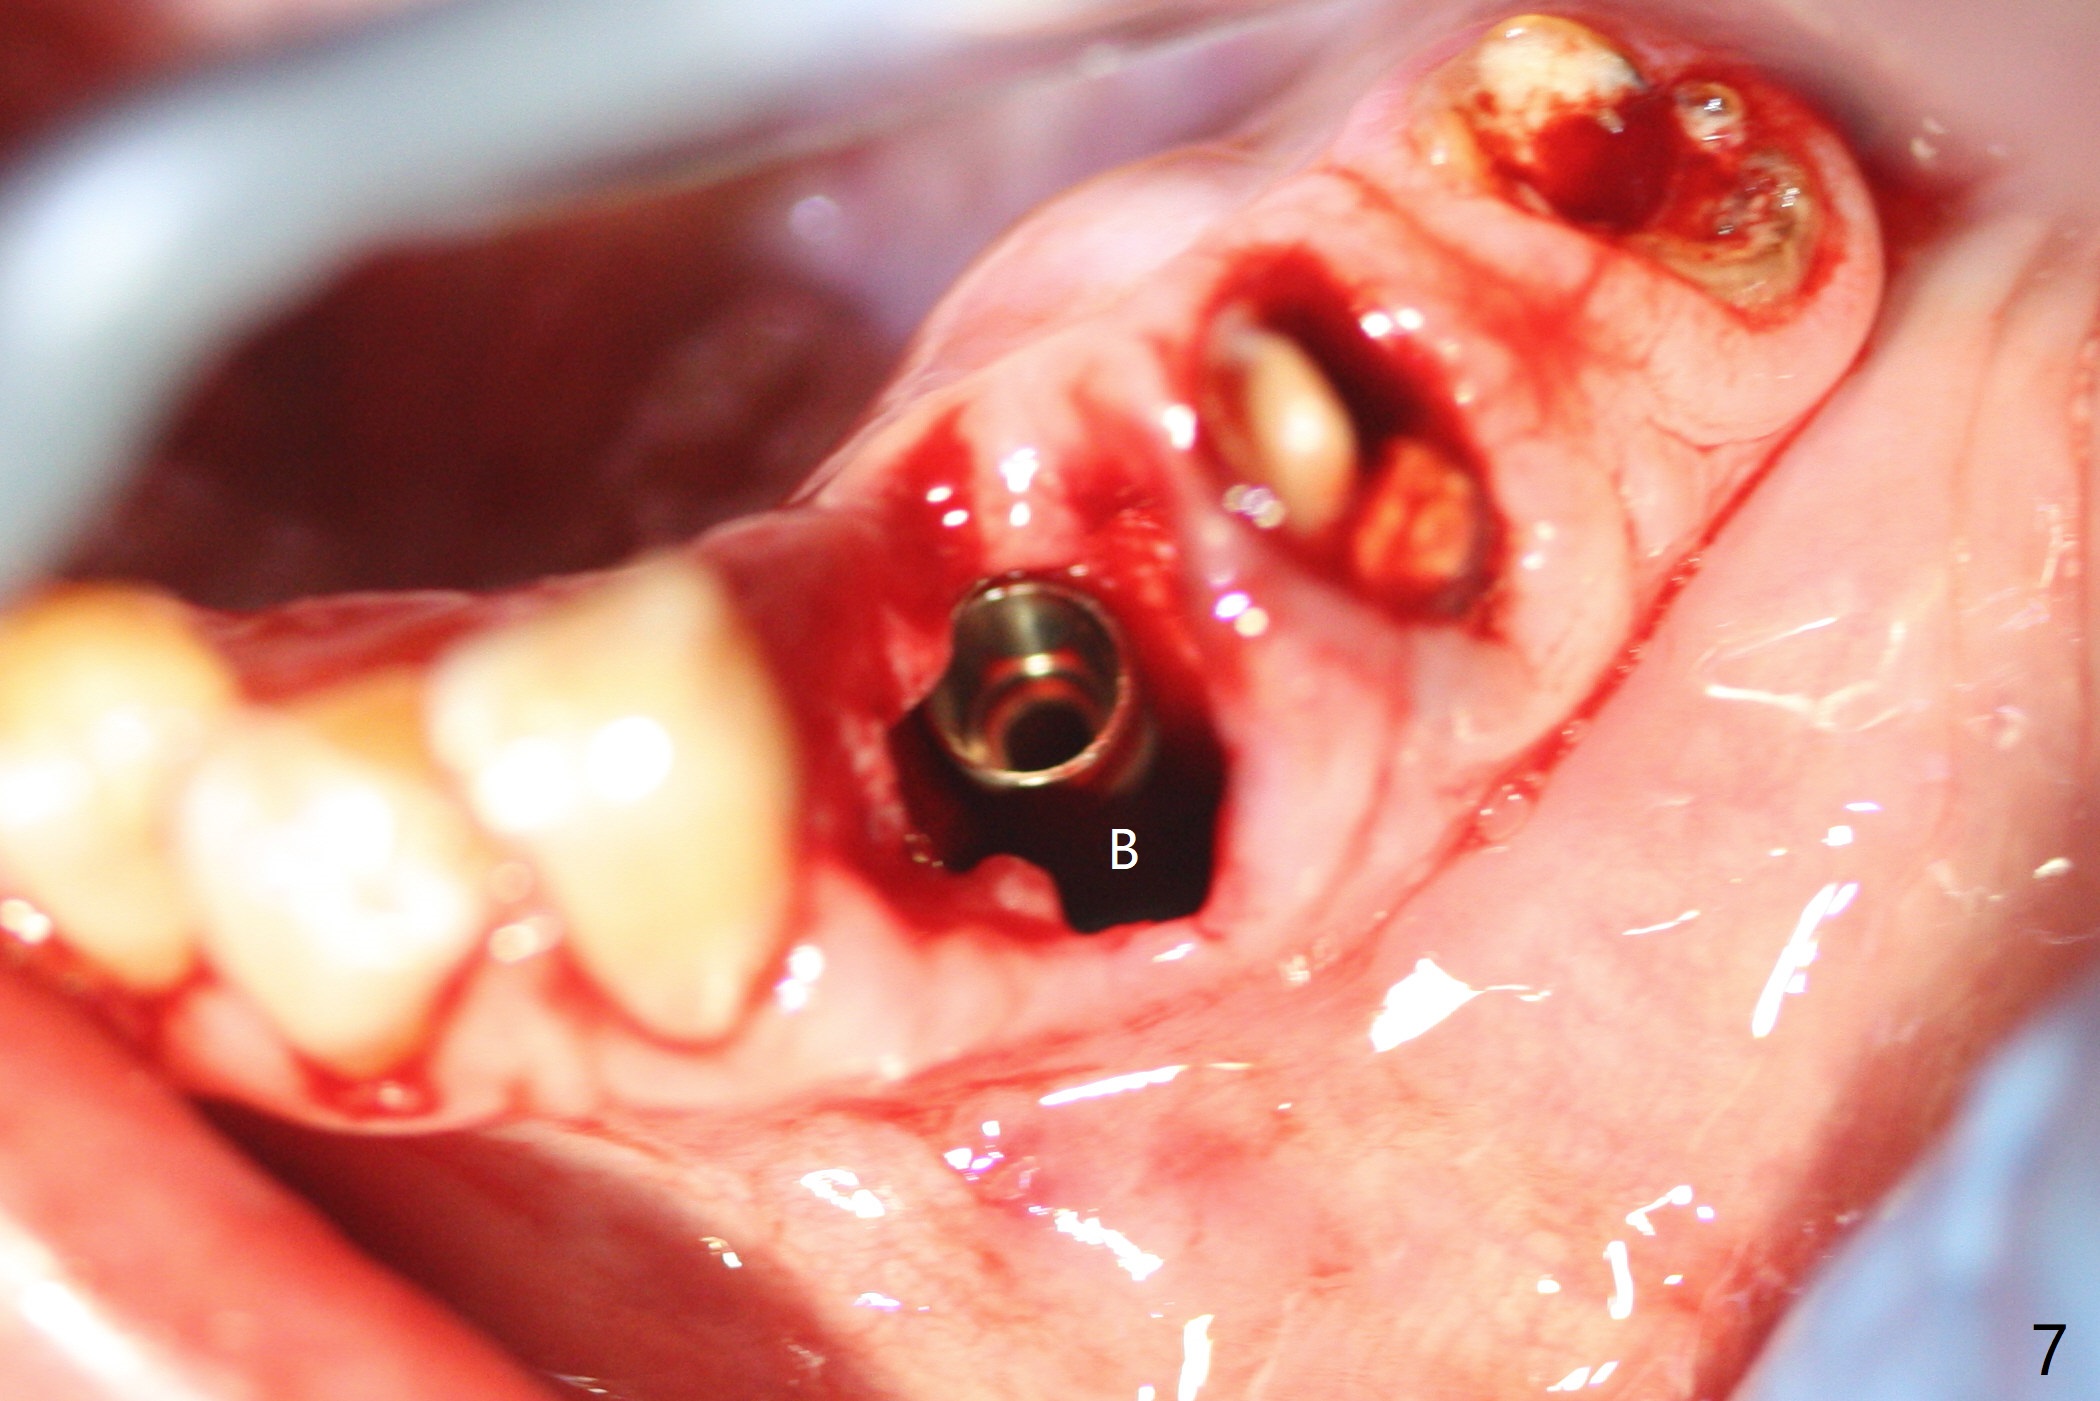

After removal of the split residual roots at #22 (Fig.1), the buccal wall is found to be defective, while the coronal portion of the lingual one (Fig.2 L) is confirmed to be more buccal than the apical portion. A vertical slot is made in the coronal portion of the lingual plate (Fig.3 *) in order to establish osteotomy lingual (Fig.4 O). The depth of the osteotomy in the apical native bone is 4.8 mm (Fig.5 CT coronal section). After the final drill (3 mm) is removed, a 3.8x16 mm implant is placed lingually for secure 2-pointed fixation (Fig.6,7, coronally: mesiolinguodistal; apically: in the native bone (Fig.9)). The essence of the lingual placement is the presence of a large buccal gap for Osteogen plug (Fig.8 yellow) and allograft (Fig.8 red, 9,10 (*)) for potential regeneration of the buccal plate. With bone graft and the overlying provisional (Fig.11 P), the buccal plate seems to have been established (*) 1 week postop. There is no obvious implant thread exposure 8 months postop (Fig.12). But the buccal plate is atrophic when the crown is cemented (~10 months postop, Fig.13).